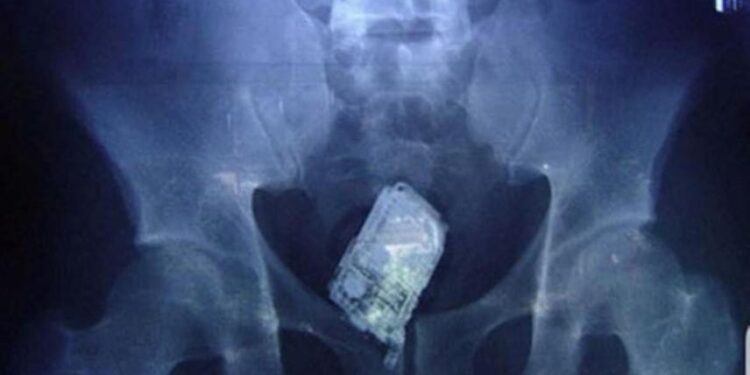

Según denuncian desde Acaip-UGT, los funcionarios penitenciarios trabajan con medios claramente insuficientes frente a este desafío. Los dispositivos cada vez son más pequeños, con materiales plásticos que escapan fácilmente a los detectores de metales, y se ocultan en los lugares más insospechados.

También se solicita la implementación de escáneres corporales avanzados, mejores protocolos de requisa, y plantillas suficientes y formadas para hacer frente al reto que supone la entrada masiva y silenciosa de teléfonos móviles en prisión.